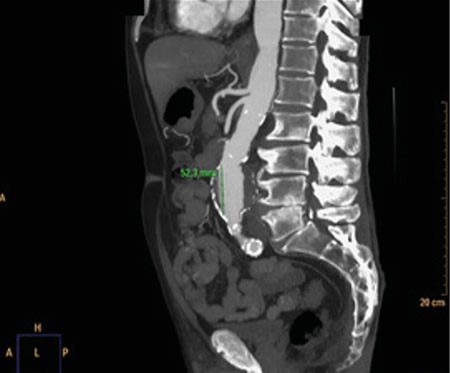

No es solo dolor lumbar: manifestación atípica del aneurisma de aorta

Not just low back pain: atypical manifestation of aortic aneurysm

La rotura de aneurisma de aorta supone el síntoma principal en hasta un 25 % de los casos de la patología de aneurisma de aorta, que constituye una entidad potencialmente mortal. También puede aparecer con menor prevalencia como lumbalgia, coxalgia e, incluso, gonalgia, no comentándolo como dolor vertebral o neuropático, sino como irritación a nivel de psoas ilíaco como primera sintomatología.

Se estima que solo en un 50 % de los casos aparece la triada clásica del aneurisma, por lo que es necesario tener un alto nivel de alerta para sospecharlo, ya que la hipovolemia puede estar contenida por un hematoma peritoneal.

Figura 2